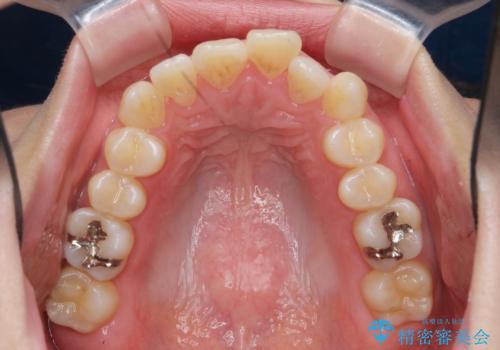

上下の歯は、上顎の歯が相対的に前に位置する咬合関係で押し出されるように前歯に角度がついている状態です。

咬合関係の改善、前歯の角度、がたつきを改善するため、マイクロインプラントを用いて上顎の奥歯を後方へ移動させていきます。